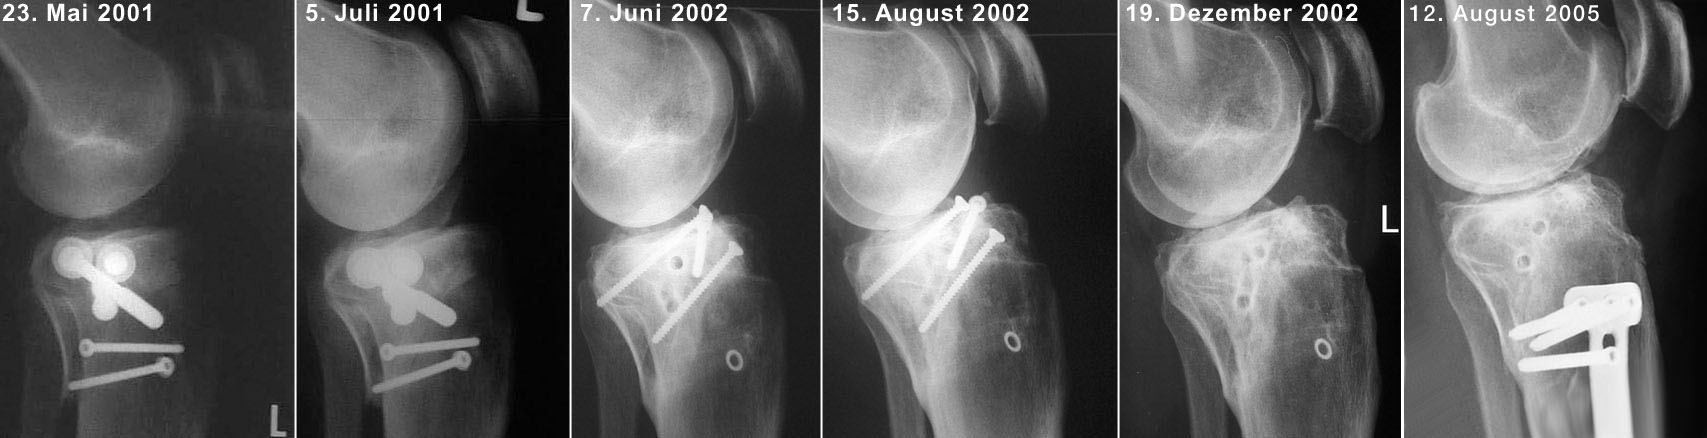

Fibula / Tibiakopf Mai 2001 bis August 2005